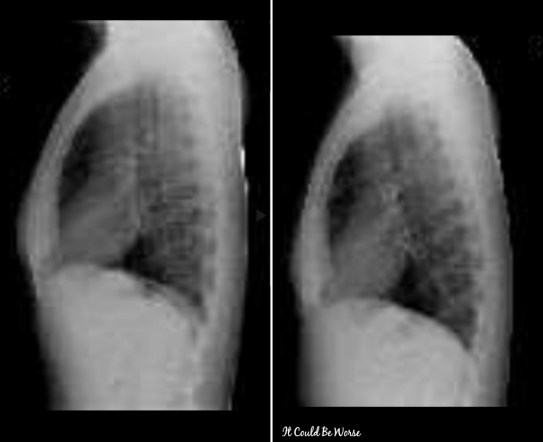

After speaking with my care team, they decided that we could remove the tube and let me breathe a little while before getting an x-ray, just to make sure everything was okay on my insides and that my lungs fully expanded back up. Below is a comparison of my x-rays, before and after surgery.